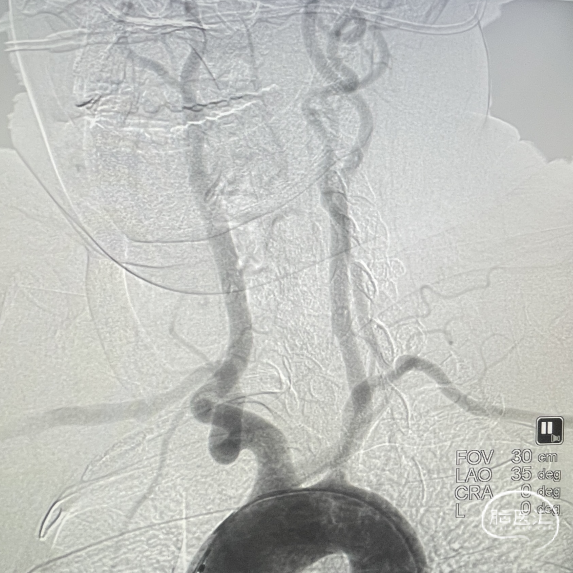

术前DSA影像:造影显示患者右侧大脑中动脉闭塞。

DSA—主动脉弓造影

右侧颈内动脉造影—M1段闭塞

建立三轴系统,导引导管置于右侧颈内动脉C1段,6F 125cm WAVE-track抽吸导管置于眼动脉附近,QUEEN-track微导管在微导丝引导下越过闭塞段入M2上干。